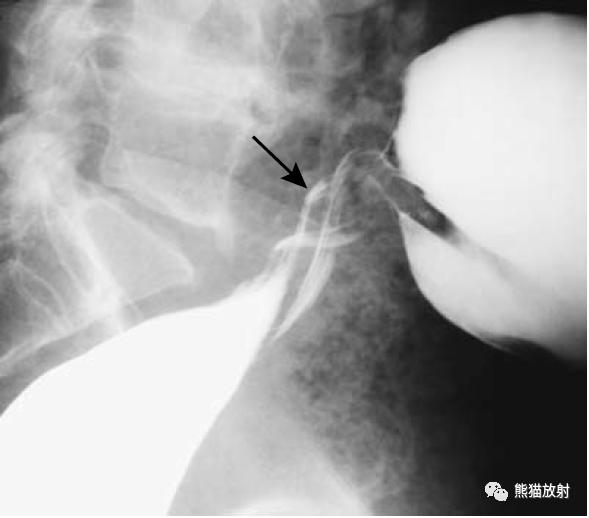

乙状结肠扭转。消化道造影侧视图可见乙状结肠局部走行扭曲(箭头)。